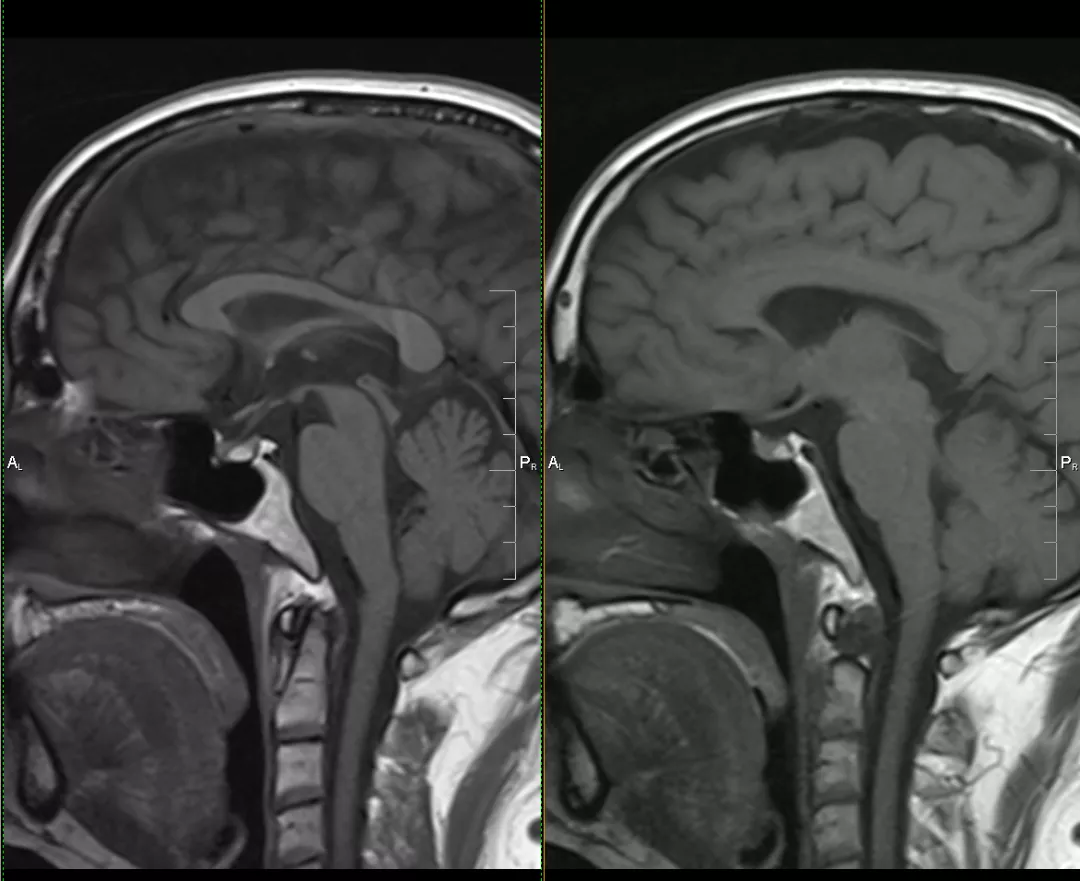

case 6:m/57y 眩晕反复发作

case 7:M/49y 头晕 3D

T1WI 高、T2WI 等信号结节,增强未见强化

case 8:F/56Y 头晕 1y

case 9:女,28y,头晕头痛

case 10:偶然发现,无症状,10 年后再次检查发现病灶消失

case 11:正常垂体位于囊肿下方——「杯中卧蛋」征